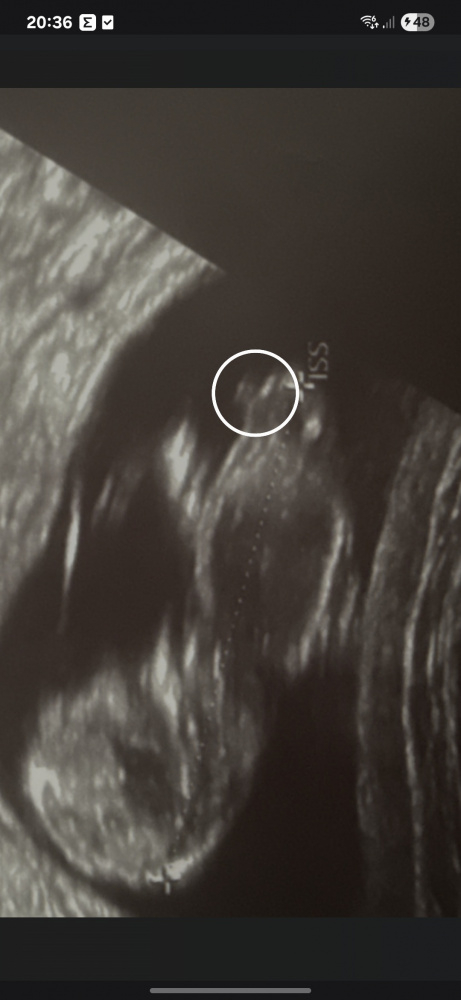

Hier siehts aus als wĂĽrd der Nub wegstehen was fĂĽr einen Jungen spricht. Aber ich bin keine Expertin.